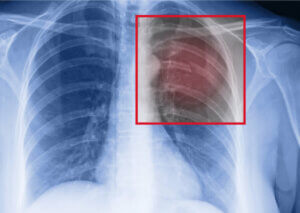

If you’re an athlete and you have a suspicion that you’re suffering from a stress fracture in your ribs, the first thing to do is to consult with a doctor. They can take an x-ray of the thorax to properly diagnose the injury and evaluate it’s extension.